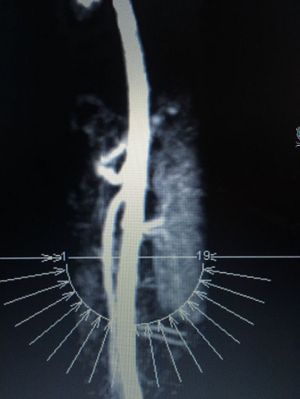

12 year old female presents with stomach pain, extreme bloating, nausea, and trouble eating. Was diagnosed with median actuate ligament syndrome a year earlier and has a ligament release on celiac artery. This is an image of the aorta with the celiac and SMA artery coming off. Do you notice anything off? What’s you’re diagnosis?